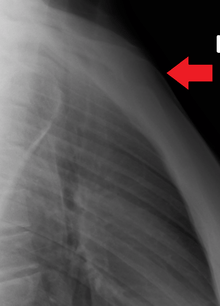

Position of sternum (shown in red). Animation.